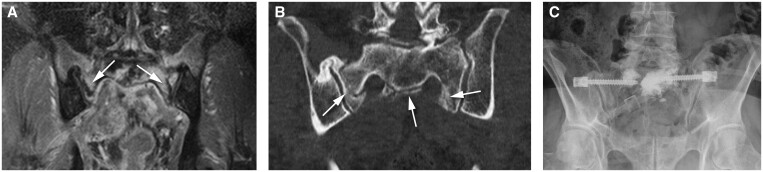

Methods: Clinical data, including details of all surgical procedures and radiotherapies of patients histologically diagnosed with sacral chordoma between 2008 and 2023 available at our database, were retrospectively reviewed. Inclusion criteria were as follows: availability of diagnostic, treatment planning and follow-up magnetic resonance and/or computed tomography scans, and completed treatment. Scans were re-evaluated for the presence and location of IF defined as linear abnormalities with(out) bone marrow oedema (BME)-like changes.

Results: From 48 included patients (29 male, median age 66, range 27-85), 22 were diagnosed with 56 IF (45.8%). IF occurred 3-266 months following the treatment. All sacral and iliac bone IF had vertical components parallel to the SI joint. Twenty patients had bilateral and 16 unilateral IF. BME-like changes were visible in 46 IF (82.1%, 0.80, P ≤ .001). In 13/56 IF (23.2%), BME-like changes were seen prior to IF diagnosis; in only 1 patient, BME-like changes did not develop into an IF. Thirty-nine IF (84.7%) occurred within low-dose volume and 7 (15.3%) outside of irradiated volume in 16/44 irradiated patients. Six IF occurred in 1 patient treated with surgery only.